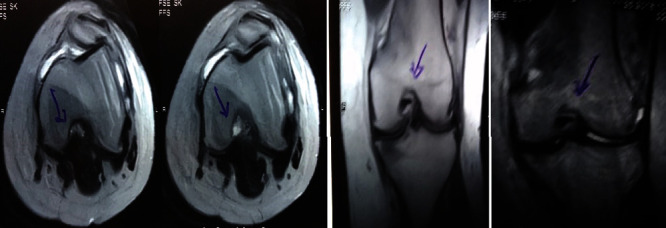

治療后一個月進(jìn)行隨訪。在第一次細(xì)胞治療后,患者的疼痛明顯減輕。第二次療程后,她沒有疼痛,并注意到運(yùn)動范圍有所改善。持續(xù)的物理治療也觀察到下肢肌肉力量的增加。從治療開始(11個月前)到最后一次隨訪(4個月前),患者按照建議的飲食和基于運(yùn)動的方案減重了11公斤。因此,她現(xiàn)在整體身體健康,能夠更舒適地進(jìn)行日常生活活動。表3顯示治療前后的MRI檢查結(jié)果。人物的圖1和的和圖2顯示半月板撕裂的治療前和治療后(1年后)圖片。觀察到損傷程度的改善圖2。